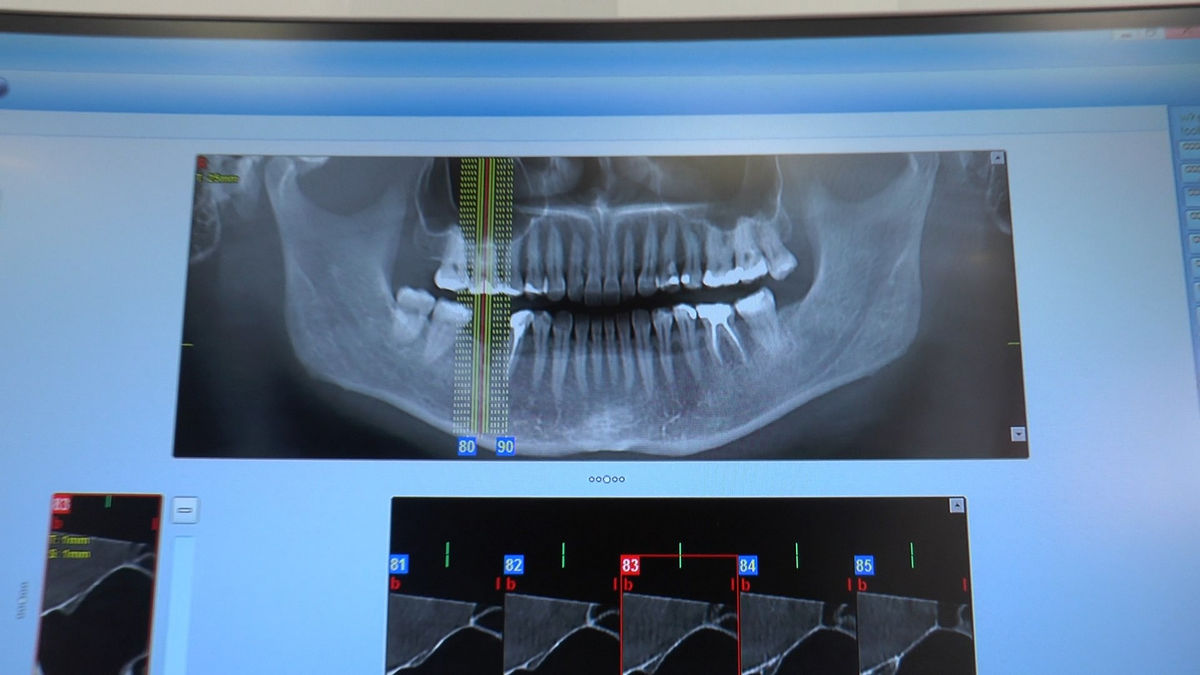

Practiculum Implantologii – Sezon V/B, sesja 8, część 4